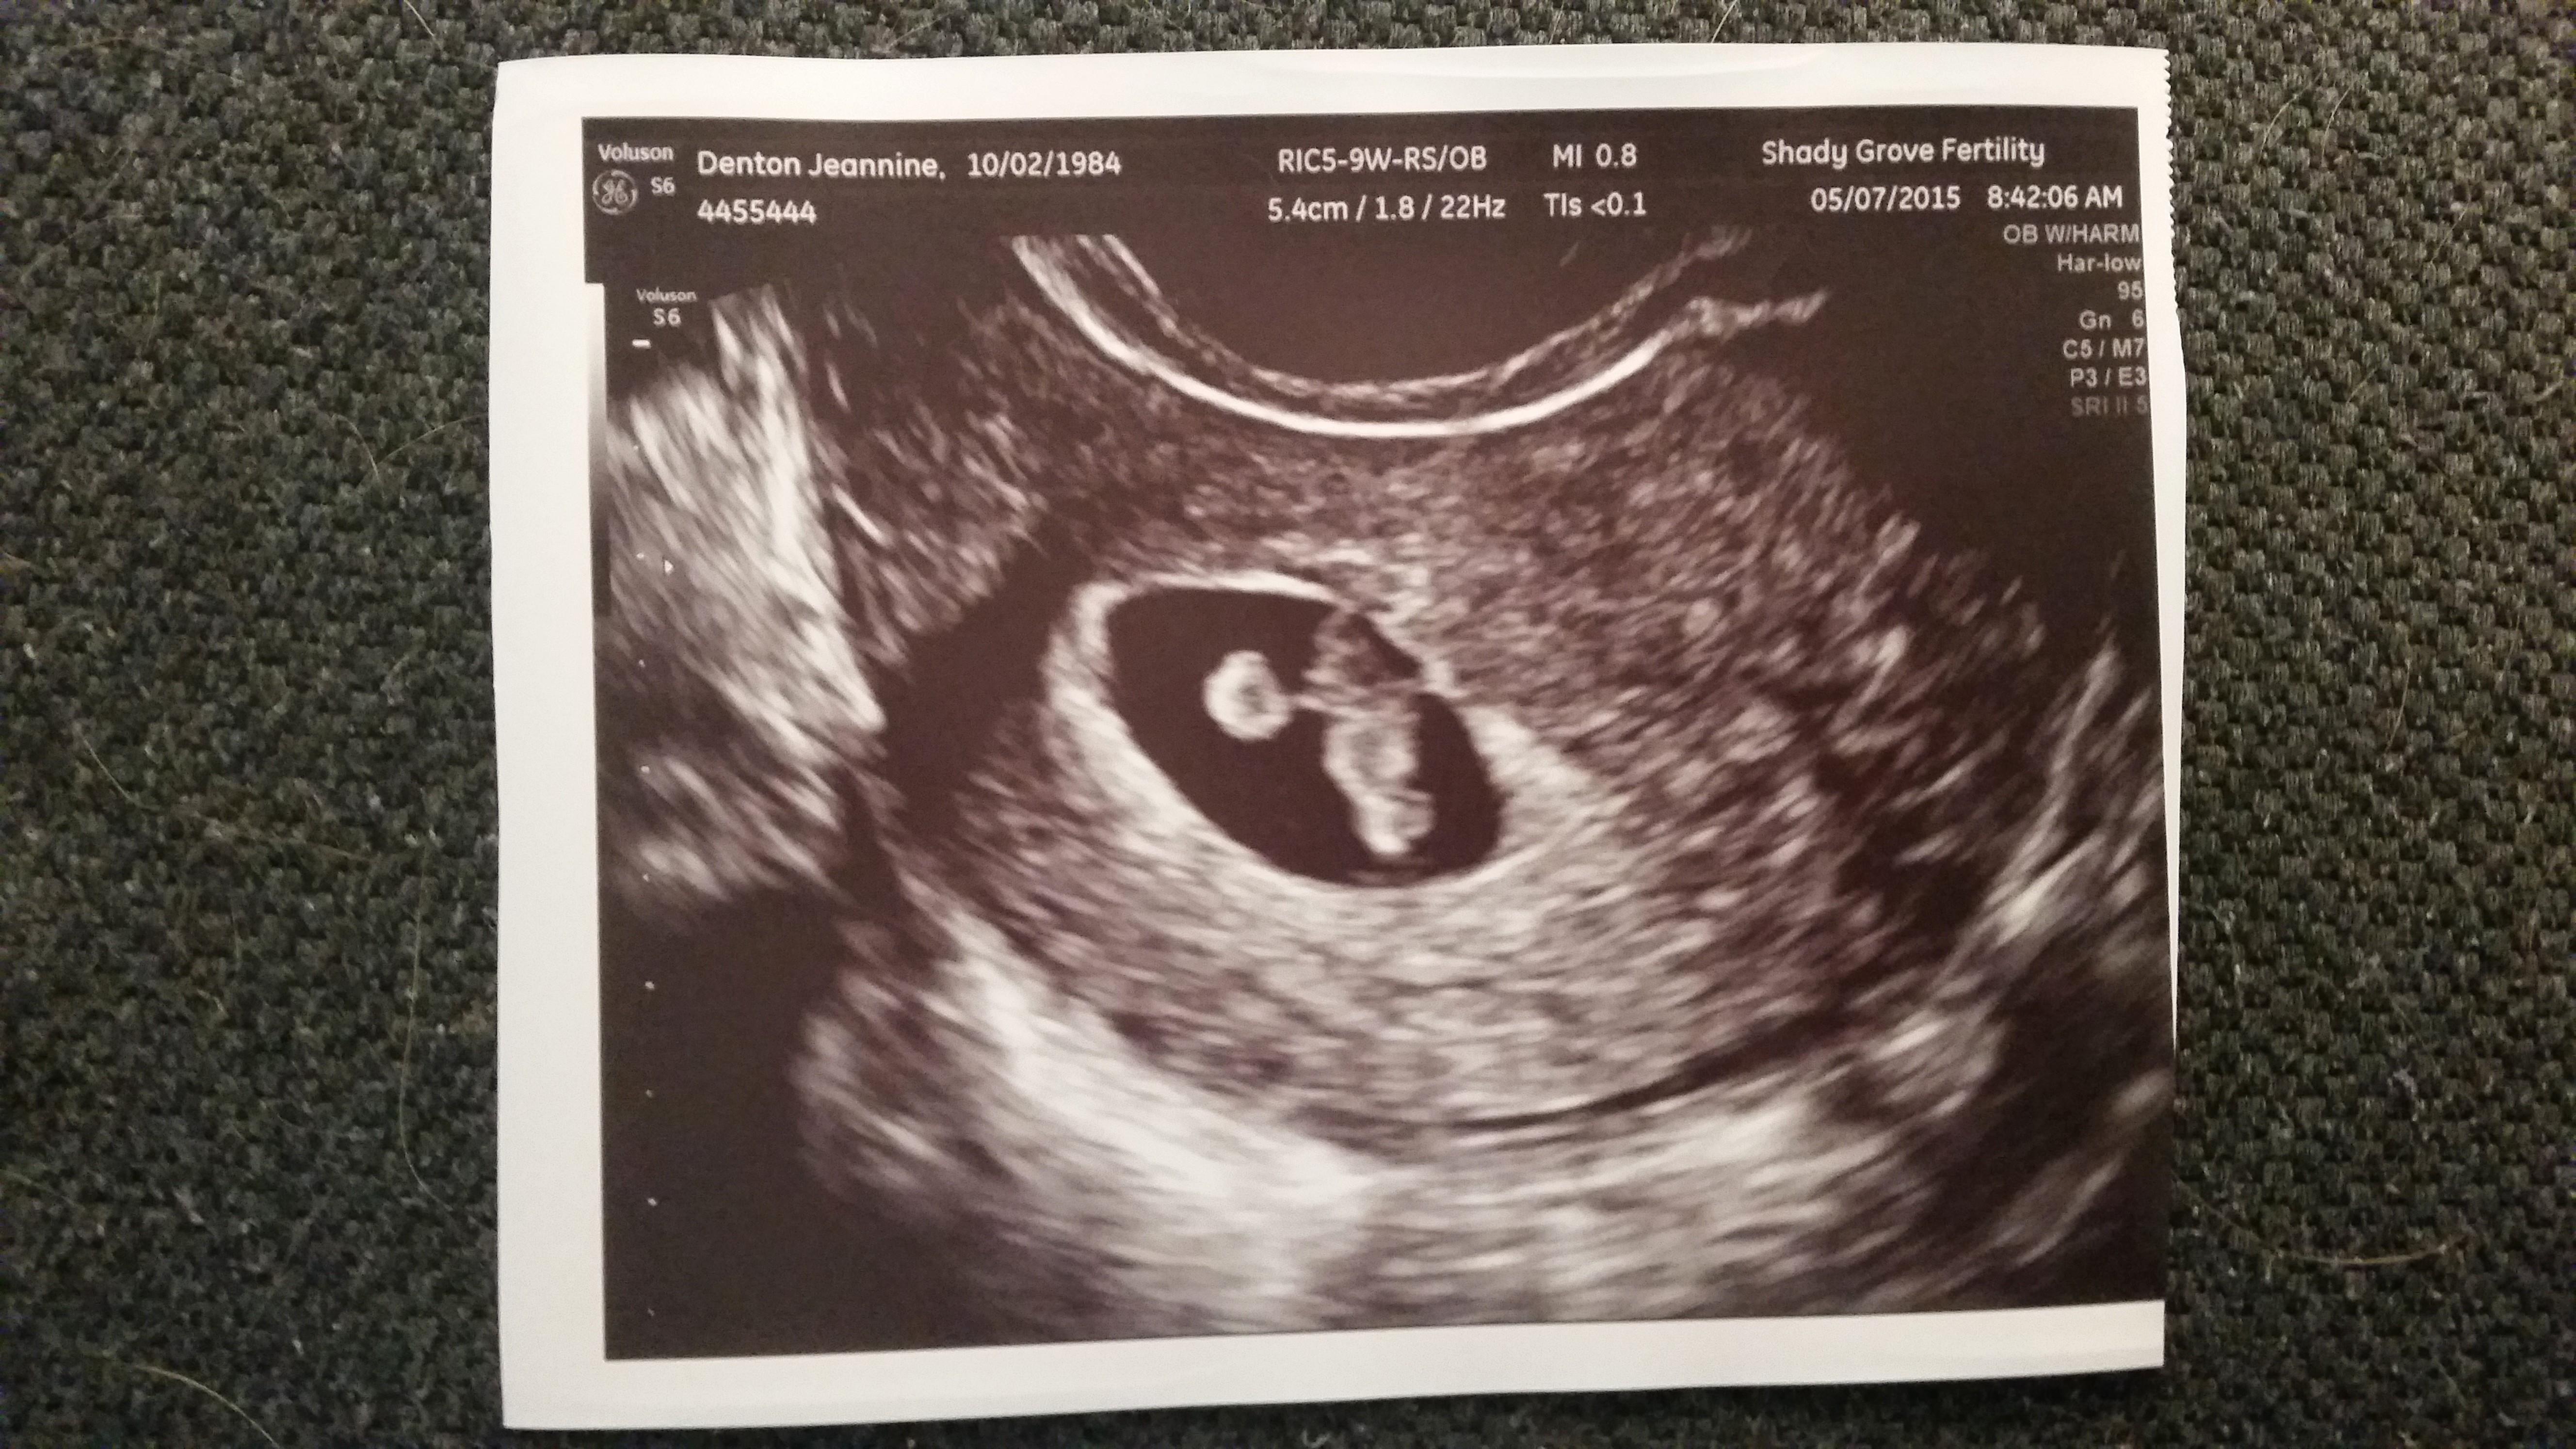

10w1d they zoomed in so I could see baby better, love my little human.. Still think the best was when my cousin goes congratulations your having a human